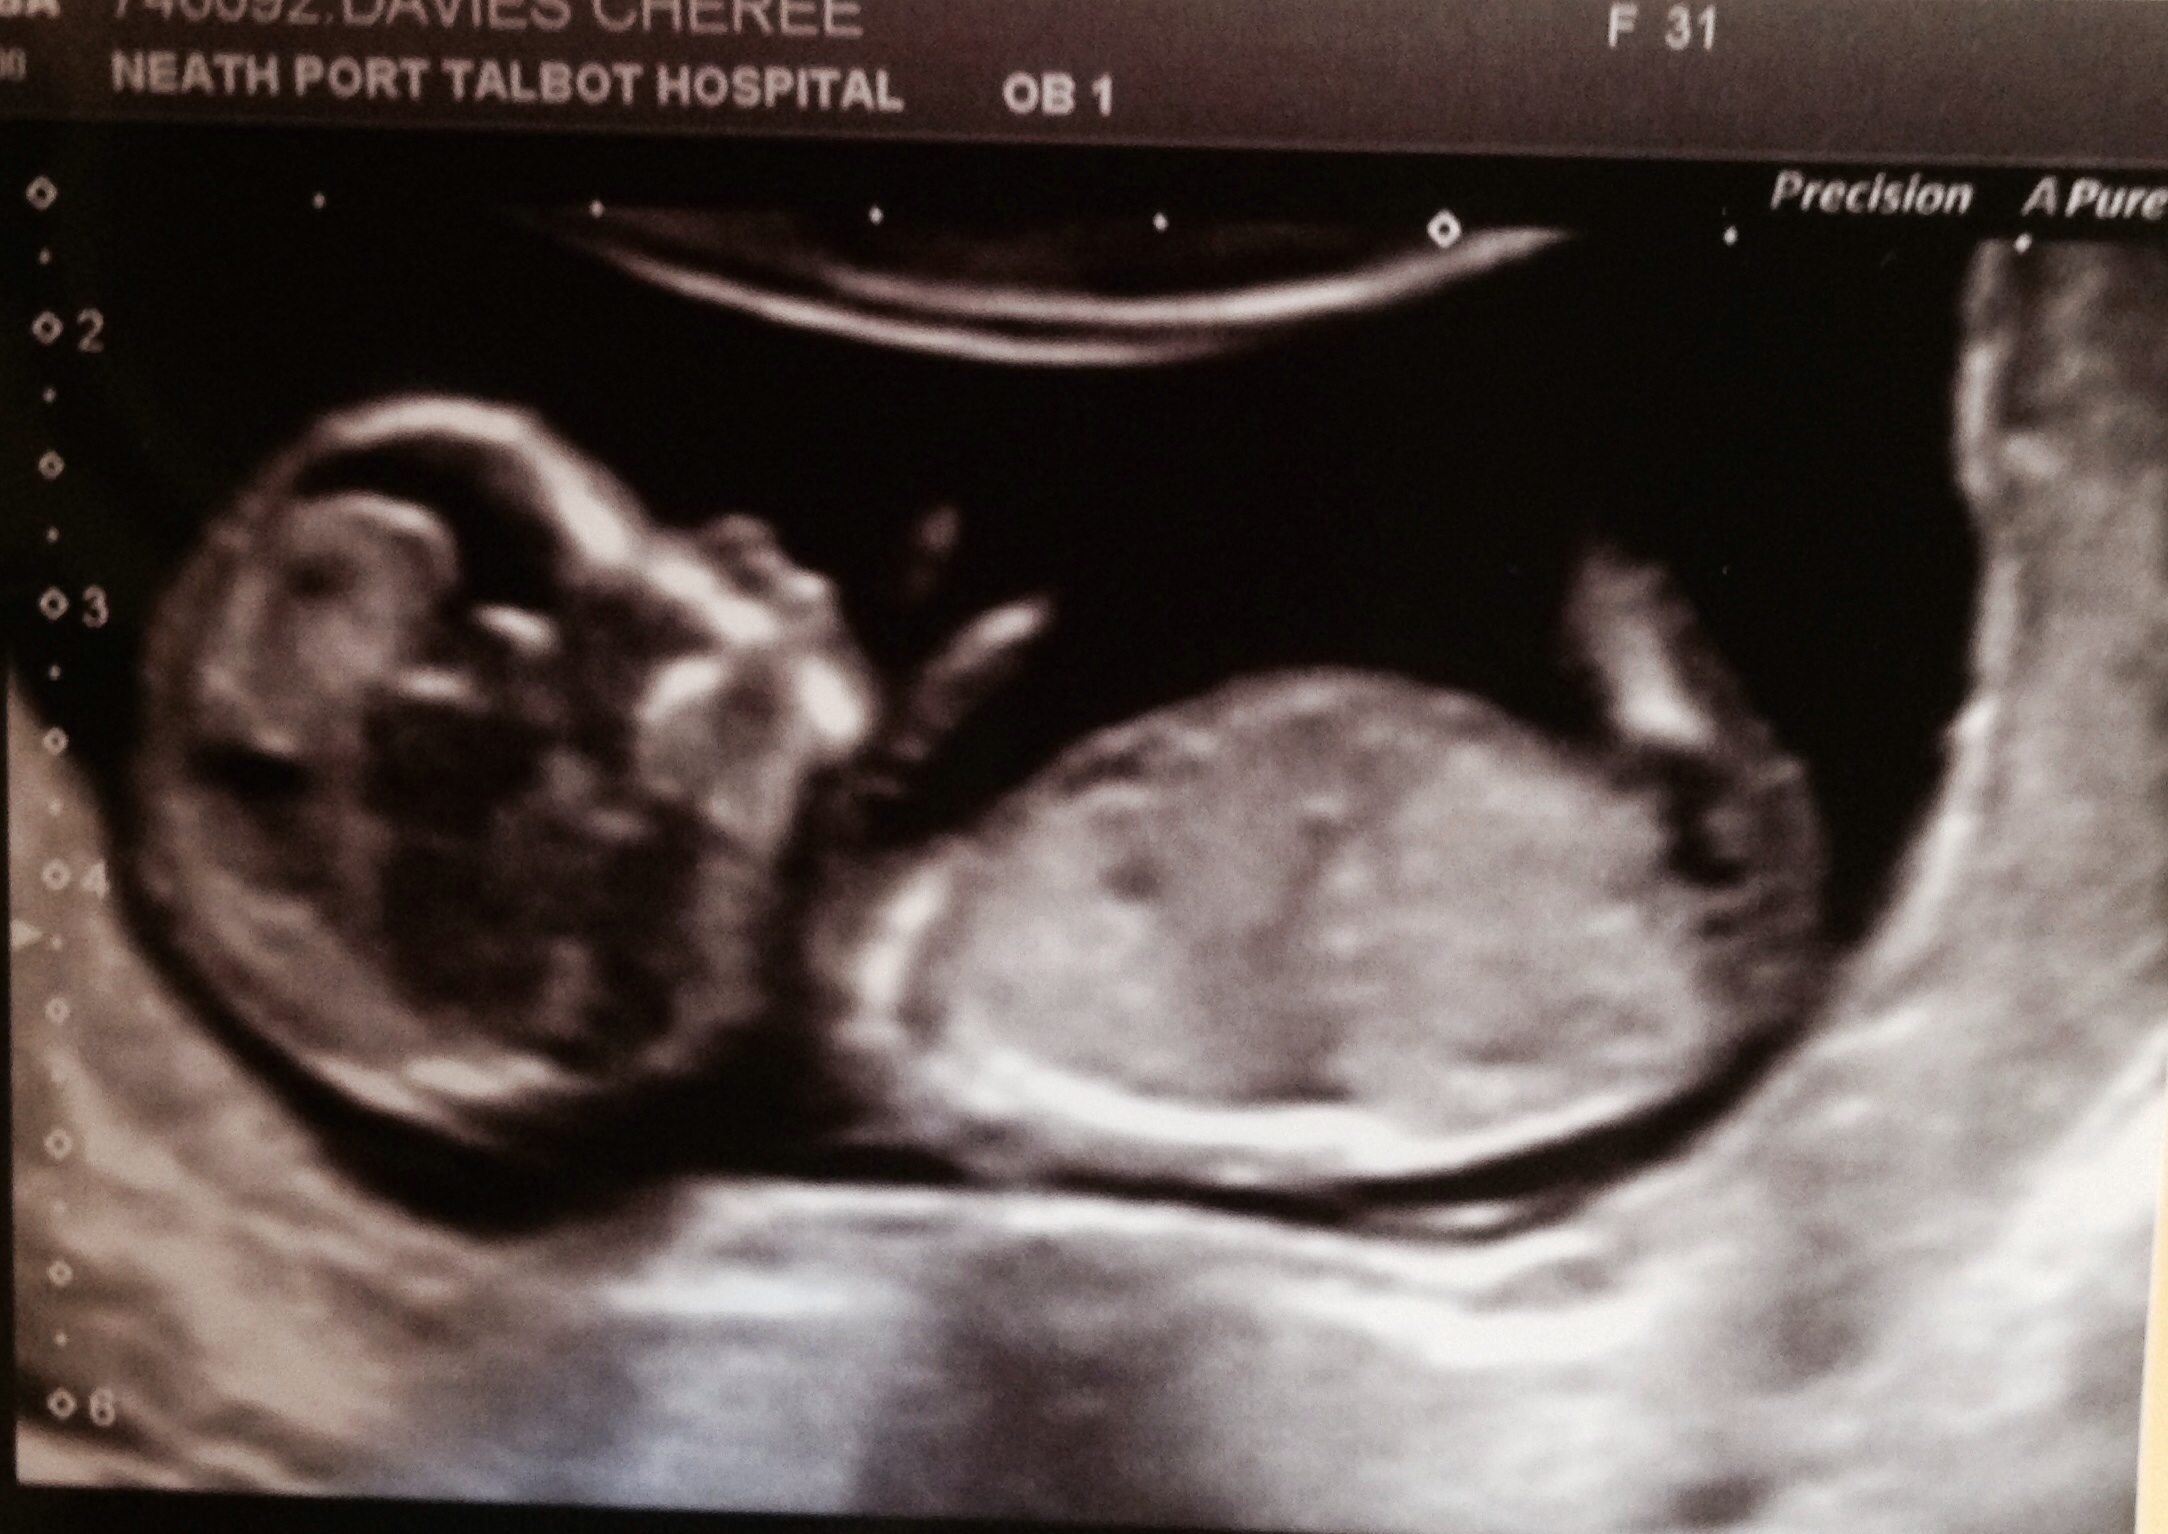

Boy or girl guesses please?

13 week scan 😄

13 week scan this was done

I say girl because I think the 2 dark white lines are possible nub and the chin is very girly. Could be wrong x

Aw thank you for you input really appreciate it my daughter had same shaped nub.. Just nice to see what others think